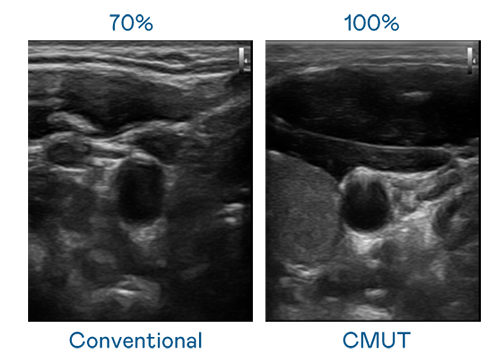

CMUT 技术是一种用电容式微机电元件来产生超音波讯号的技术。与传统 PZT 压电式技术相比,CMUT 频宽增加 30%,更宽频的超音波讯号让影像解析度大幅提升,是实现高影像品质医疗超音波扫描、促进精准医疗发展的关键技术。

大频宽带来超清晰影像

超音波影像的解析度高低,首先取决于探头能发出的讯号频宽。AG官网 CMUT 可提供高清晰的超音波讯号,提供高频宽、高灵敏度、影像纹理细节更高的超音波影像,协助医护人员缩短影像判读时间及利用精准的医疗影像进行诊断。